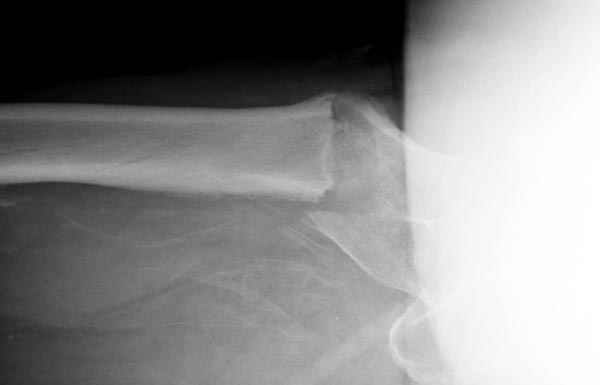

Здесь сканнированные снимки импланта и операционные снимки больной.

На этом снимке процесс компрессии нижним болтом.